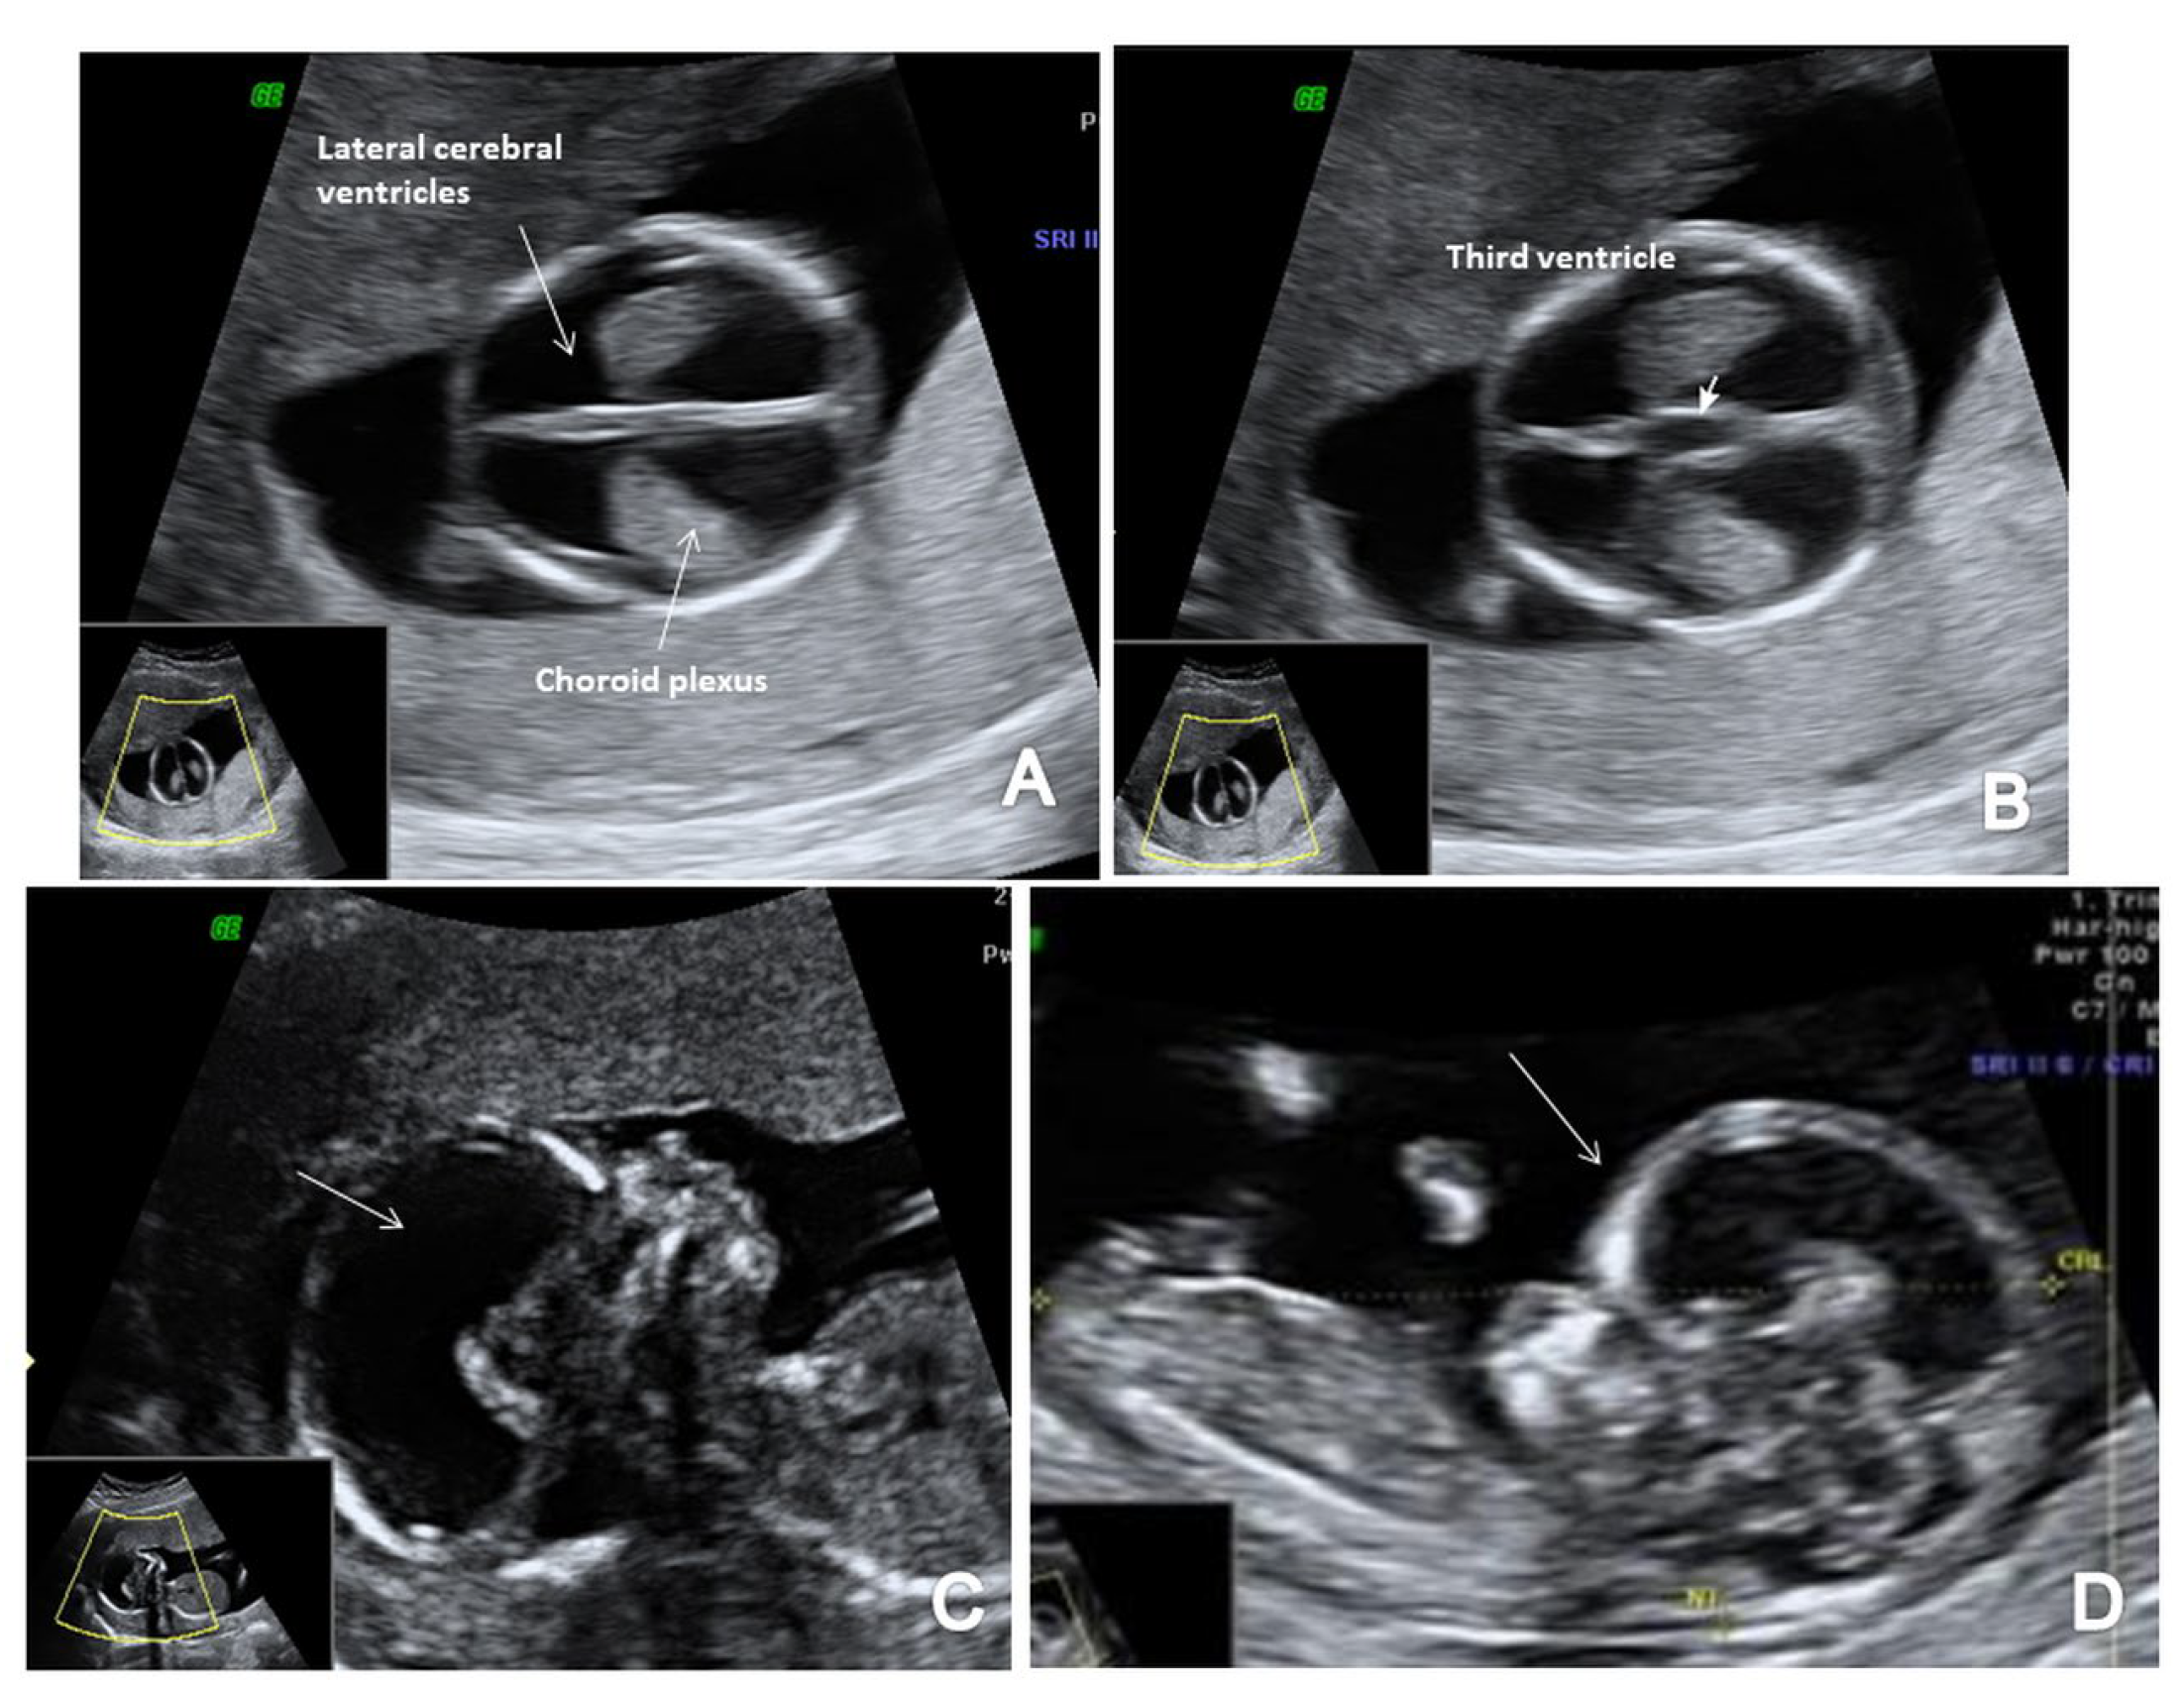

In terms of FTAS, we adopted a standard protocol that added the guidelines for basic FT screening [8] and several features for a more detailed structural assessment at this gestational age. The detailed scanning protocol included two axial planes of the brain (at the level of the choroid plexus and third ventricle and the level of the cerebral peduncles and aqueduct of Sylvius) and the sagittal view of the fetal face for the evaluation of the posterior brain complex. The scanning protocol aimed to assess the contour and shape of the fetal skull, the choroid plexus shape and relative filling of the ventricles and the aspect of the lateral cerebral ventricles (Figure 1A). We noted the presence of the third ventricle (Figure 1B) and the aspect and position of AS (Figure 1C), the presence of the CM and the fourth ventricle (the anechogenic area between the posterior border of the brain stem (BS) anteriorly and the choroid plexus of the fourth ventricle posteriorly) (IT) [13]. We investigated the presence of posterior and caudal displacement of the mesencephalon by searching for the ‘crash’ sign in the thalamic axial plane [14]. The BS/BSOB ratio was subjectively evaluated and measured when it appeared abnormal [15], and the presence of CM was noted (Figure 1D). Fronto-maxillary angle was measured in all cases, as part of the genetic screening, but narrow-angle cases were suspected also for neural tube defects [16]. In all cases, the spine was also evaluated in two-dimensional (2D) longitudinal planes, recording its regularity and the continuity of the underlying skin layer (Figure 1E).

Figure 1.

The FTAS protocol for CNS evaluation: (A) transverse view of the brain showing the contour and shape of the fetal skull, choroid plexus (arrow) and the filling of lateral cerebral ventricles (arrow); (B,C) further evaluation of the cerebral ventricular system, in transverse planes of the brain showing the third ventricle (B) and aqueduct of Sylvius (C) (arrow); (D) mid-sagittal view of the brain showing the thalamus (Tha) and the measurements for the brain stem (BS), the fourth ventricle (IT), cisterna magna (CM), the nuchal translucency (NT) and the brain stem–occipital bone ratio (BSOB); (E) longitudinal view of the spine regularity and underlying skin (arrow).